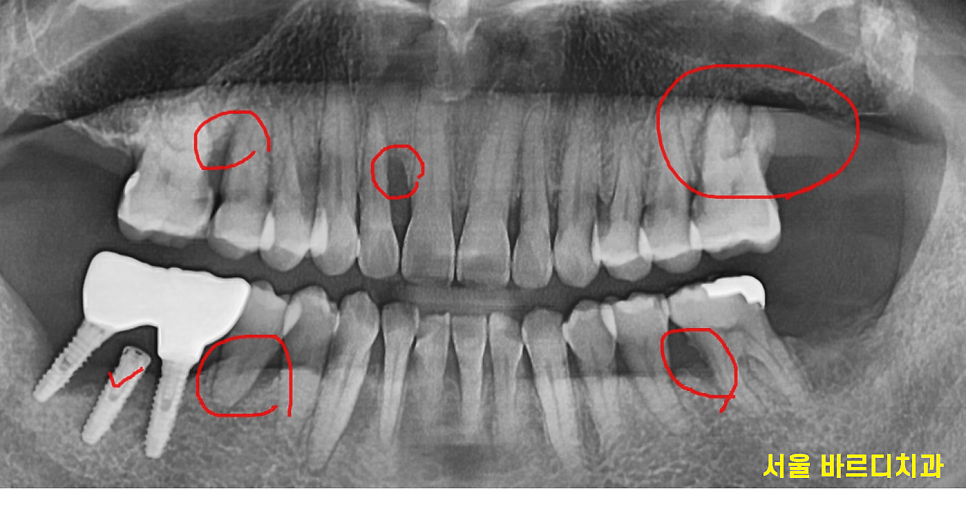

잇몸 뼈가 많이 녹은 x - ray를 보여드릴께요~

240430

빨간색 동그라미 친 부분이

잇몸뼈가 다 녹은 부분입니다.

이 정도가 되면 사실은 이를 뽑아야하는데요.

240920

오늘 환자분도 가장 문제가 되는 부분부터

발치 후 임플란트 치료를 하셨답니다.